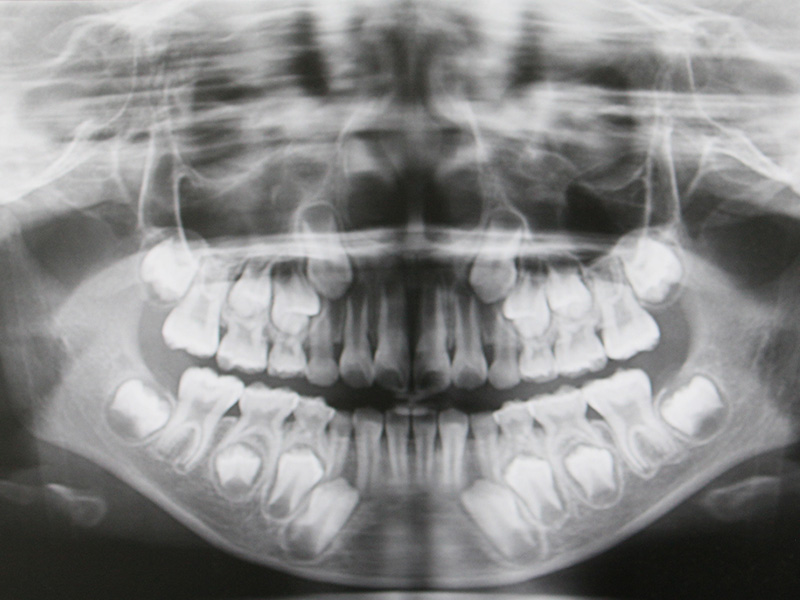

頭部X線規格写真(セファログラム)を用いた、

より精密で正確な矯正治療をいたします

矯正治療はとても繊細な作業を必要とします。当院ではセファログラムを使い、顔面・頭部を撮影し、「矯正前」「矯正中」「矯正後」のレントゲン写真を同規格で撮影し、変化を確認しながら治療に当たります。「上下顎の大きさとずれ」「顎の形」「歯の傾斜角」「口元のバランス」などを確認し、計画に沿って経時的に見ていきます。

カウンセリング・頭部X線規格写真(セファログラム)

患者様の症状、ご希望、ご要望など、カウンセリングでお聞きした上で診察を始めるよう心がけております。頭部X線規格写真(セファログラム)の撮影をさせていただき、診断させていただきます。

できる限り患者様の負担の少ない方法で治療させていただきます。セファログラムを撮影して、変化を確認しながら綿密に矯正を進めていきます。